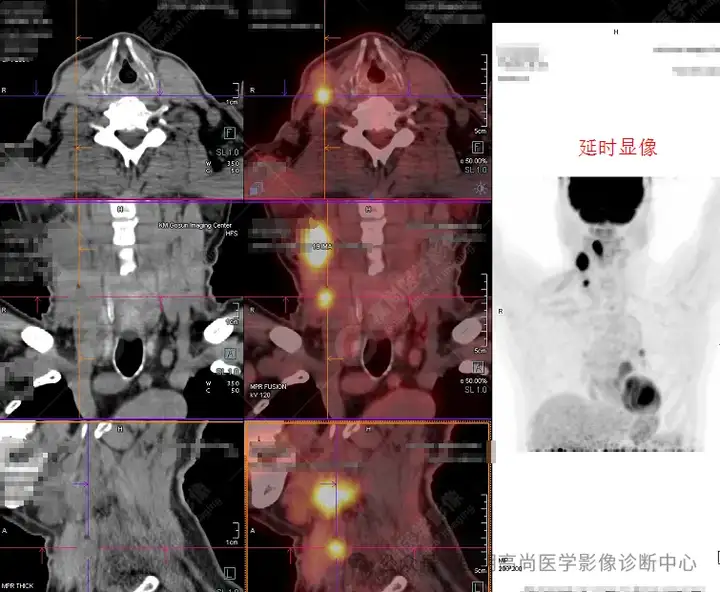

右颈部多发高代谢淋巴结1

右颈部多发高代谢淋巴结2

2、 双颈颈Ⅱ、Ⅲ、Ⅳ、Ⅴ区、左肺门(10组)及纵隔(4、5组)多发淋巴结显示,其中右颈Ⅱ、Ⅳ区、左肺门(10组)及纵隔5组淋巴结明显增大并糖代谢持续不同程度增高,符合转移淋巴结表现,余淋巴结反应性增生可能,建议随诊。

通过 PET/CT影像,肺、食管等器官无明确实体性肿瘤,诊断口咽来源恶性肿瘤可能性大(回访明确为口咽部恶性肿瘤,已经开始相应治疗)。